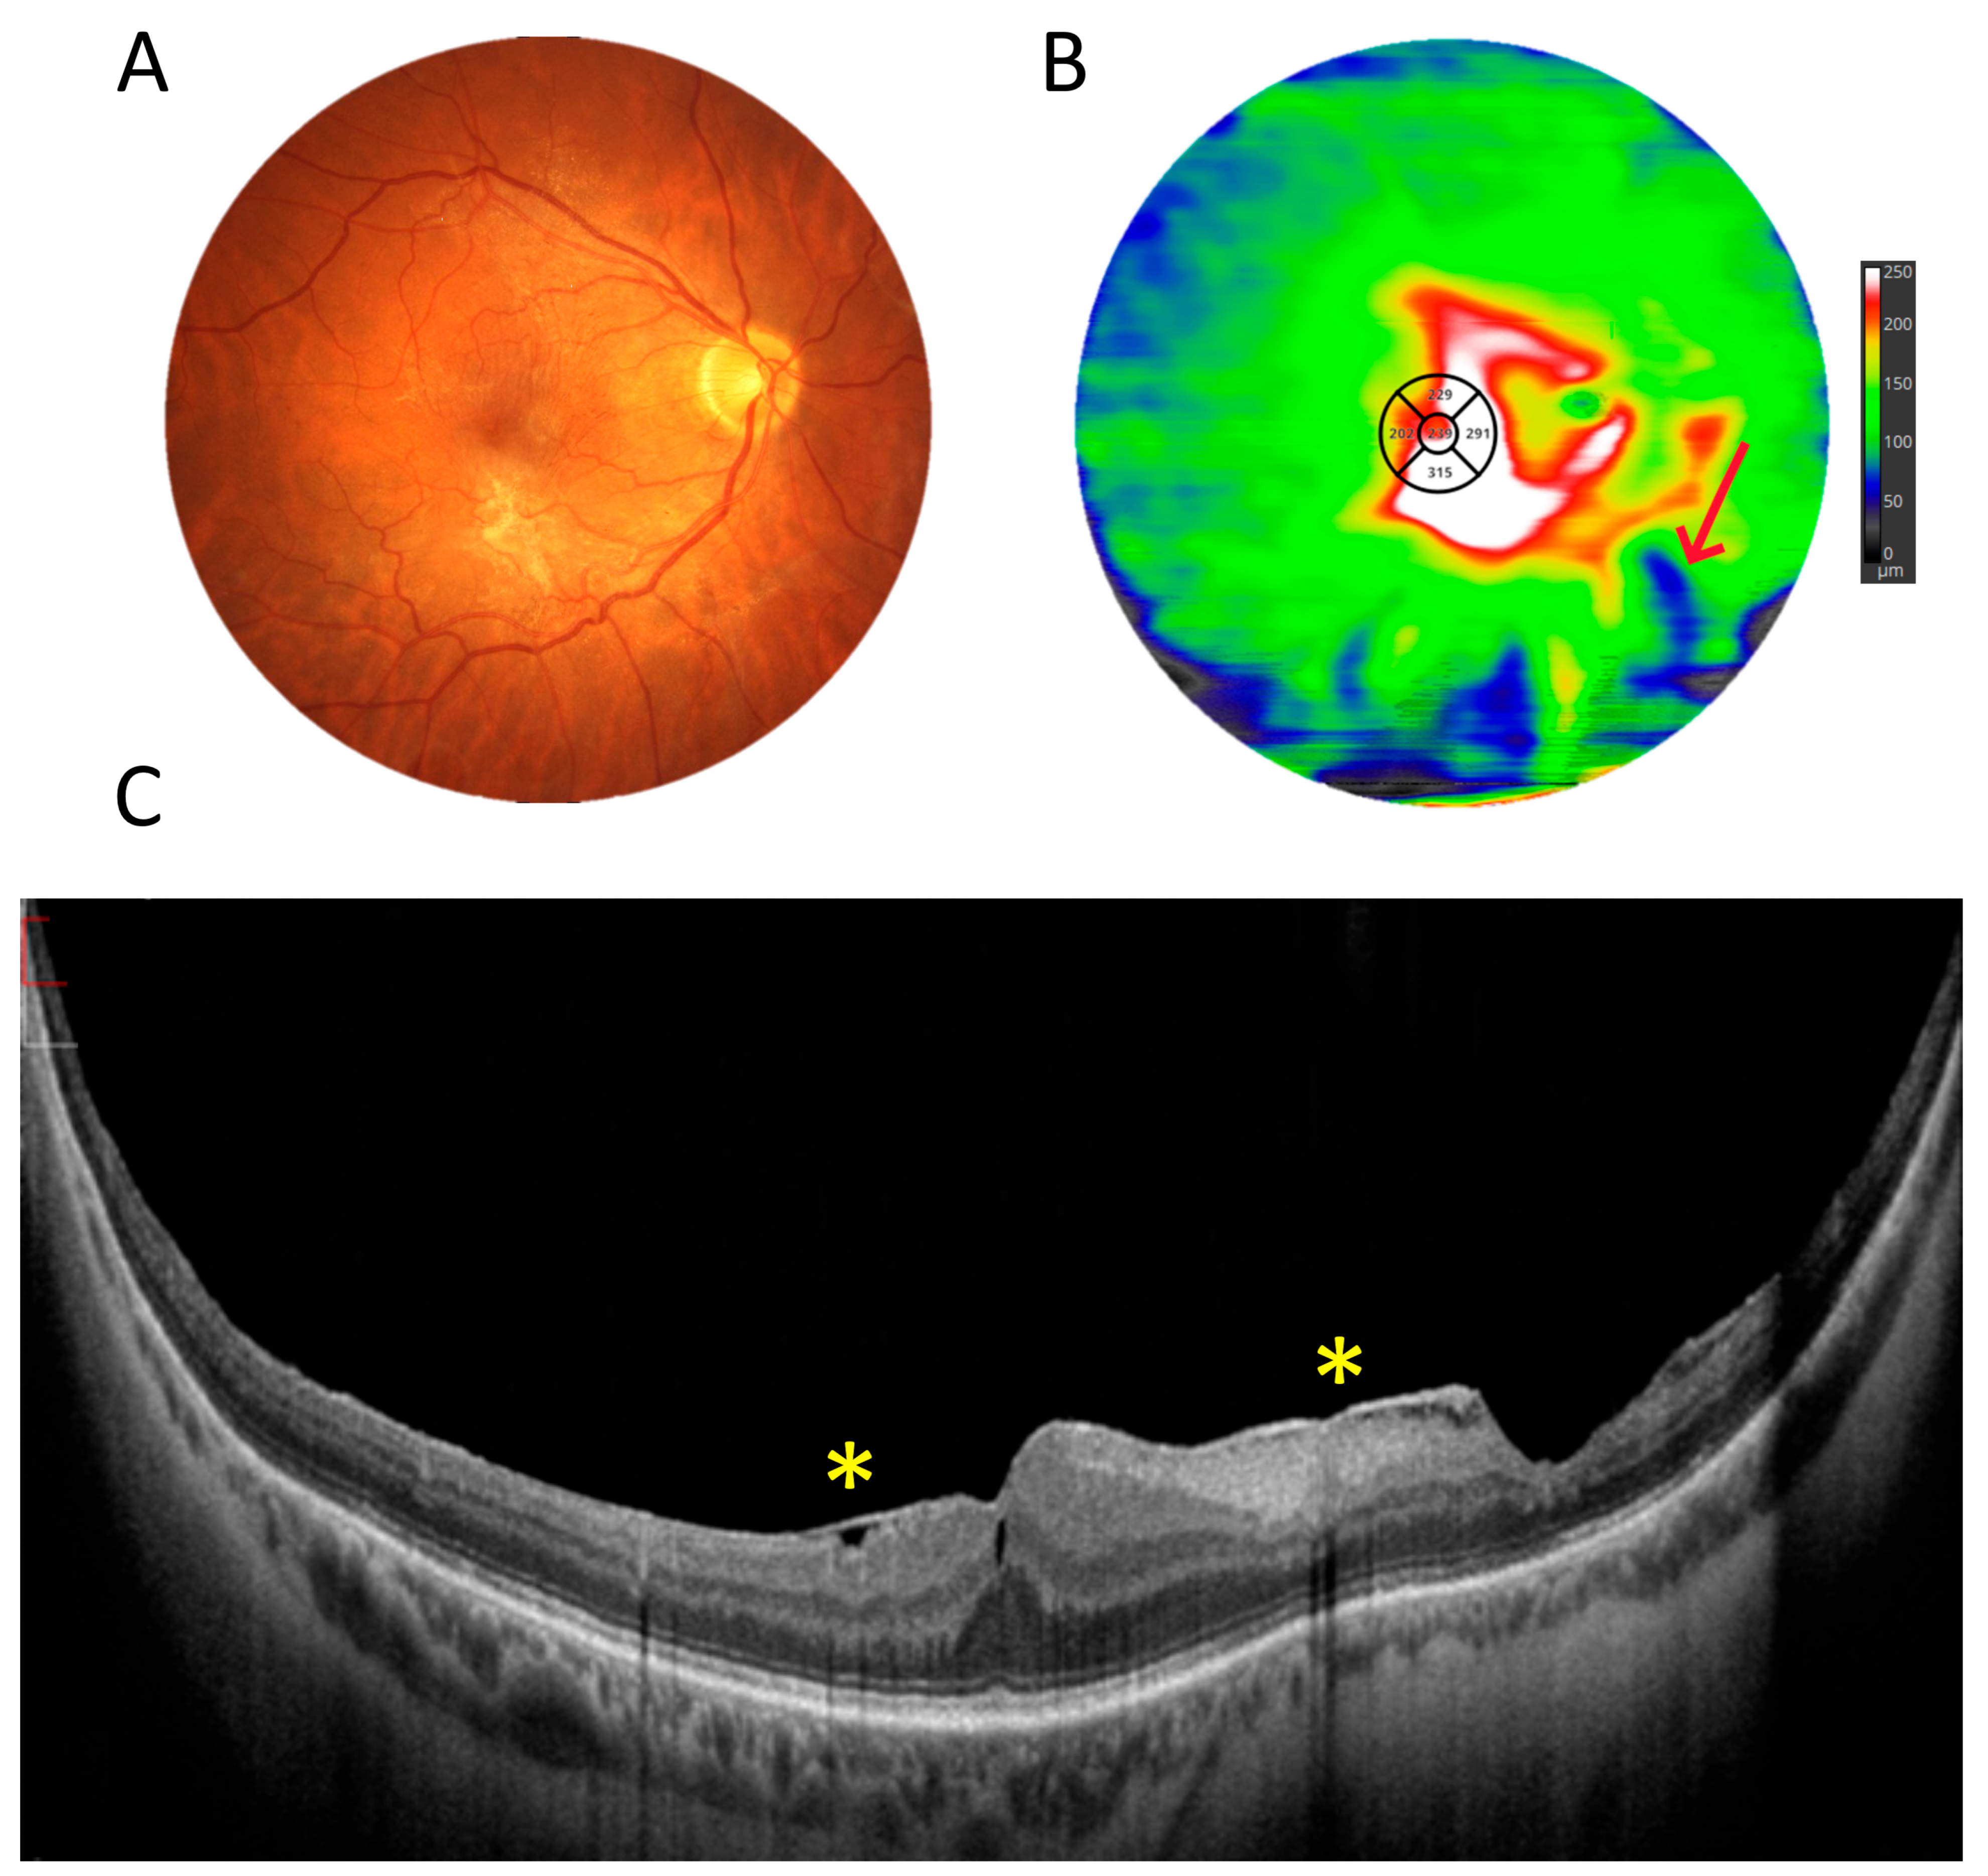

3.5. Retinal Thickness Measurements

3.1. OCT Measurements

3.3. OCT and Angio-OCT Measurements